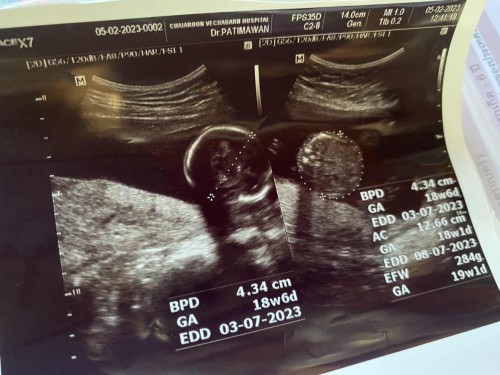

ตั้งครรภ์17week เเต่น้ำหนักลูกไปขนาดเด็ก19weekเเล้ว😂

เเบบนี้คือน้องตัวใหญ่ใช่ไหมค่ะ เเม่ๆบ้านไหนเป็นเเบบนี้บ้างค่ะ ผลตรวจNIPTบอกน้องเป็นเพศชาย ท้องนี้เเม่เเทบจะไม่ได้บำรุงเลยทานปกติเหมือนตอนไม่ท้องเน้นไข่ กับปลา เเละหมู น้ำหนักเเม่ก็ยังเท่าเดิมไม่ขึ้นค่ะ